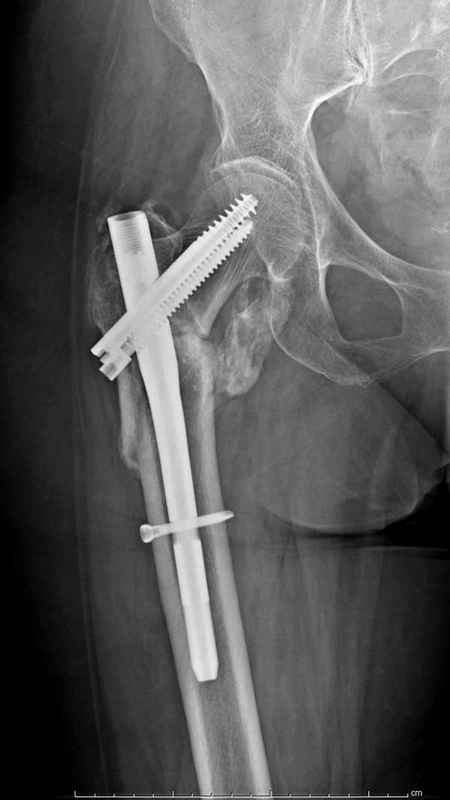

Re: Чрезвертельный перелом бедра

Здесь 83 года, травма в результате падения